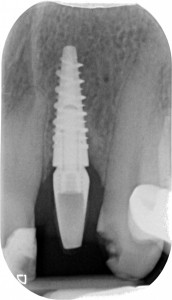

“Guarda questa lastra, cosa ne dici? Sta bene questo impianto?”

gestione dei tessuti molli -rx

PERFETTO direi io, neanche un po’ di riassorbimento. Credo che tu sia d’accordo con me.

La signora Rosetta ha finito questo lavoro dal suo vecchio dentista esattamente 6 mesi fa. Appena messo la corona definitiva ha iniziato a lamentarsi di un fastidio continuo. Il collega, non so in base a quale presupposto teorico, ha rimosso il definitivo e rimesso il provvisorio.